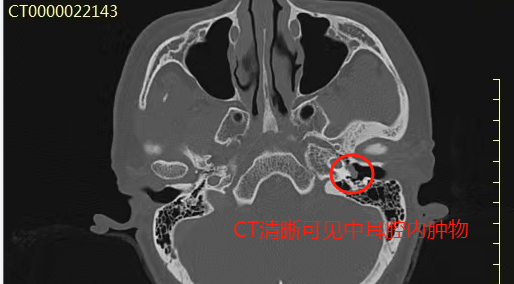

检查发现,曹女士左侧耳膜虽完整,但透过耳膜可以看到中耳腔内长有红色肿瘤,紧紧贴着耳膜,在耳内镜下还可以看到耳膜有着与耳鸣和心跳节律一致的搏动。随后的CT、MRI检查,再次验证了张主任的猜想:鼓室球体瘤。